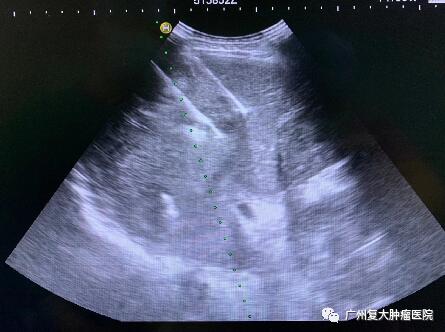

影像图片显示

图2